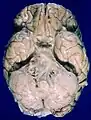

![]() Human brain bottom view. Orbital gyri shown in green. | |

Human brain bottom view. Orbital gyri shown in red.